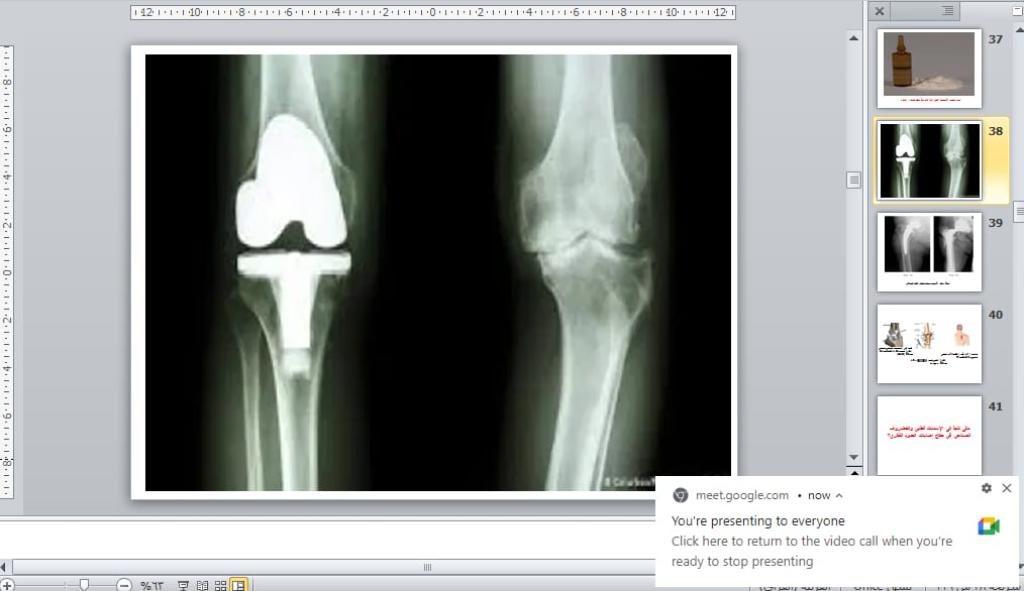

برعاية السيد رئيس جامعة الموصل الأستاذ الدكتور قصي كمال الدين الاحمدي وبإشراف السيدة عميد كلية العلوم الأستاذ الدكتورة هيام عادل إبراهيم وضمن نشاطات التعليم المستمر في كليتنا ، أقيمت في قسم الفيزياء الطبية دورة علمية عبر الفضاء الإلكتروني بعنوان ” الاسمنت الطبي في مفهوم الفيزياء الطبية ” للفترة 3 – 5 كانون الثاني 2023 .تضمنت محاضرات اليوم الأول التي القاها أ.م.د. قصي خطاب عمر الاسمنت الطبي كعلاج فقرات العمود الفقري ، الاسمنت الطبي يستخدم في جراحة المفاصل و هشاشة العظام ، الاسمنت العظمي العلاج الأمثل لآلام المفاصل بدون جراحة فضلاً عن الاسمنت العظمي مكوناته وخواصه الفيزيائية .بينما تطرّق في اليوم الثاني عن تشخيص الاسمنت الطبي بكل أنواعه باستخدام عدة تقنيات منها ( باستخدام الأشعة السينية التقليدية ، باستخدام جهاز CT scan ، باستخدام الرنين المغناطيسي ، باستخدام جهاز PET المسح البوزتروني ) .وفي اليوم الثالث والأخير القى م.د. محمود أحمد محمد فخري محاضرة عن بعض خواص الاسمنت الطبي وطرق تحضيره سريراً ، ومدى تأثر التركيب النهائي له بطرق التحضير الآنية ، وماهي فائدة بعض الاضافات لتركيبة الاسمنت الطبي ، كما تضمنت المحاضرة حقنة الاسمنت الطبي لمعالج كسور الفقرات الناتجة عن هشاشة العظام بالدرجة الأولى أو بعض الحوادث أو الأمراض الأخرى المؤدية إلى ضعف الفقرات وظهور هذه الكسور.شعبة الإعلام والعلاقات العامةالجمعة 6 كانون الثاني 2023